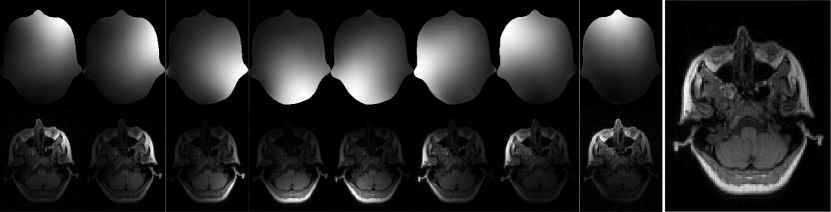

Refer to caption

Figure 4: Reconstructed images and corresponding error maps for Cartesian, Poisson-disc, and uniform random sampling for simulated (top) and noisy data (bottom). All sampling schemes used an undersampling factor of 4. Error maps have been scaled by a factor of 40 (simulated) and 4 (noisy) to aid visibility.

Figure 2 shows the coil image and the corresponding sensitivity map for all receive channels as well as the combined image. Figure 3 shows the combined power function and the Frobenius norm of the cardinal functions for different sampling patterns. While for Cartesian 2×2222\times 2 and Poisson-disc sampling the power function is small everywhere inside the sampled region indicating that interpolation error is small, the situation is different for Cartesian 4×1414\times 1 and uniform random sampling: Where larger gaps appear in the sampling pattern, the power function has high values. The power functions themselves are bounded by the diagonal elements of the kernel. This bound is approached in regions where the cardinal functions go to zero, i.e. far from acquired samples, and corresponds to a situation where nothing is known about the k-space value. The bound for the combined power functions is 6.55306.55306.5530 for the kernel used here. Consistent with this upper bound, the maximum values observed near the boundary in the computed maps are 6.48026.48026.4802 for Cartesian 4×1414\times 1, 6.39216.39216.3921 for Cartesian 2×2222\times 2, 6.37976.37976.3797 for Poisson-disc, and 6.42776.42776.4277 for uniform random sampling. Computing the maximum in a smaller inner region of size 305×230305230305\times 230 far from the boundary, the maximum values are 0.61540.61540.6154, 0.052520.052520.05252, 0.10870.10870.1087, and 4.33034.33034.3303, respectively. The last number highlights the fact that high values are attained even inside the sampled area for uniform random sampling. While the error bound for Poisson-disc sampling is twice as large as for the Cartesian 2×2222\times 2 pattern, it is still very small, i.e. 60×60\times smaller than the maximum which is obtained in unsampled regions. The reconstruction results (Fig. 4) for noise-less data confirm that the interpolation error is lower for Cartesian and Poisson-disc than for uniform random sampling. Cartesian 4×1414\times 1 performs worse than Cartesian 2×2222\times 2, confirming the notion that it is usually better to distribute the acceleration along different phase-encoding directions. The structure of the error maps in k-space is predicted well by the power function for all sampling patterns (Fig. 5). It has to be noted that the power function yields only a worst-case bound (scaled by the norm of the data) which depends on the sampling pattern, but not on the actual signal. In contrast, the actual error values in k-space depend on the energy distribution of the signal and are much higher in the k-space center than in the periphery.

In addition to the interpolation error, noise is amplified during the reconstruction. Assuming Gaussian white noise, this effect is described by the Frobenius norm of the cardinal functions. In Nyquist-sampled regions, if all channels contribute equally one would expect a value of 1/N1𝑁\sqrt{1/N} because the data from all channels is averaged. Values can be much higher in case of undersampling, but can also be lower for regions very far from acquired samples. This can be seen in at the boundary of the computed maps shown in Figure 3. In agreement with the higher values of the Frobenius norm for Cartesian 4×1414\times 1 and uniform random sampling, the respective reconstruction results for the noisy data show much more noise in the reconstructed image. Again, the distribution of noise and errors in k-space has the same structure as the Frobenius norm of the local reconstruction operators and the power function predict (Fig. 5).